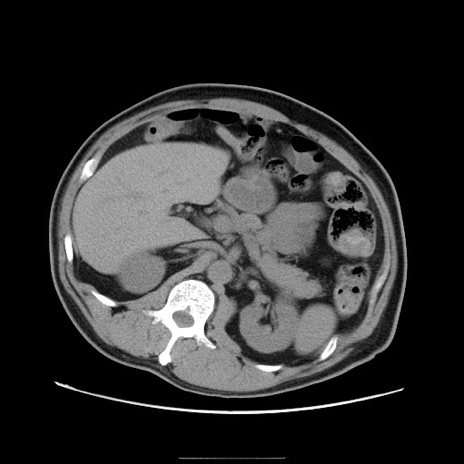

症例22(横断像)

【症例】50歳代男性

【主訴】腹痛

【現病歴】AVMからの被殻出血のため回復期リハ病棟入院中。 本日午後3時頃急に下腹部痛が出現した。

【既往歴】AVM、被殻出血、虫垂炎、高血圧

【身体所見】意識晴明、左半身不全麻痺、会話の理解は良好、36.5°C、腹部:膨隆、全体に板状硬、下腹部正中に圧痛点あり、反跳痛-、筋性防御不明、右下腹部にope scar

【データ】WBC 9400、CRP 0.06